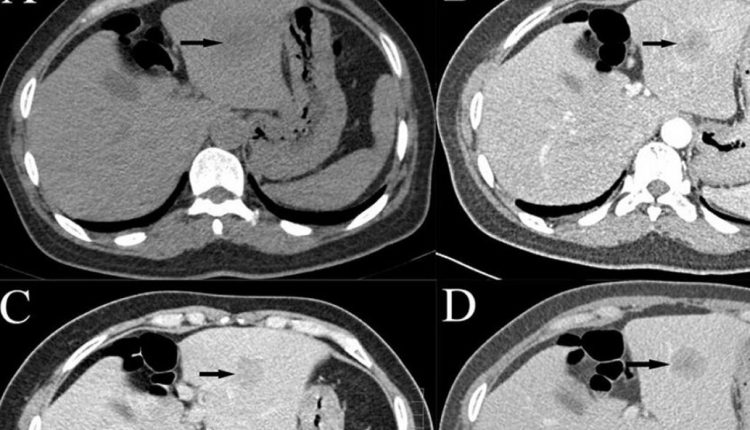

شبكة الشرق الأوسط نيوز : اقترح علماء من المركز العلمي والتكنولوجي للضوئيات الطبية الحيوية بجامعة “تورغينيف” بمدينة أوريول الروسية طريقة مبتكرة يمكن استخدامها لتحديد نوع ورم الكبد باستخدام الذكاء الاصطناعي.

وأشارت الخدمة الصحفية لوزارة التعليم والعلوم الروسية إلى أن “علماء الجامعة طوروا طريقة لتصنيف أورام الكبد بناء على تسجيل ومعالجة أطياف اضمحلال التألق (التفلور) في أثناء إجراء فحص عينة الكبد عن طريق الجلد، وذلك باستخدام خوارزميات التعلم الآلي”.

وهذه الطريقة تسمح بتحديد نوع الأنسجة البيولوجية من بين الأنسجة الصحية أو أورام الكبد بقدر عال من الكفاءة التشخيص، حيث تصل حساسية ونوعية المصنف إلى نسبة ما لا يقل عن 91٪  و79٪ على التوالي. كما أنها تجعل من الممكن فصل أنواع فرعية للورم، وبينها الأورام الخبيثة الأولية، والنقائل والأورام الحميدة بدقة إجمالية لا تقل عن 90%.

بالإضافة إلى ذلك، فإن النهج المبتكر يتيح تحديد موضع إبرة الخزعة الضوئية التي طورها أيضا العلماء في جامعة “تورغينيف”، في أثناء التدخل الجراحي البسيط والحصول على استنتاج أولي حول نوع ورم الكبد مباشرة أثناء العملية.